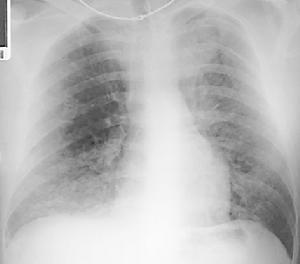

1.胸部X線檢查胸部X線片對咯血的診斷意義重大,故應作為常規檢查項目。要求多個體位投照,必要時還應加照前弓位、點片及斷層片。胸片上出現沿支氣管分布的捲髮狀陰影,多提示支氣管擴張;液平多見於肺膿腫;實質性病變多考慮肺部腫瘤。值得注意的是,在病灶大量出血時血液可被吸入鄰近氣道,此種吸入可導致肺泡充盈,形成血液吸入性肺炎。在早期易與肺部實質性病變相混淆,但血液吸入性肺炎常在1周內吸收,故再次攝片將有助於兩者鑑別。2.胸部CT是一項非侵襲性檢查,對肺功能障礙者較為安全。但對活動性大咯血患者,一般應在咯血停止後進行。與普通X線胸片相比,在發現與心臟及肺門血管重疊的病灶及局部小病灶等方面,CT檢查有其獨特的優勢。在評價穩定期支氣管擴張病人方面,胸部CT已基本取代了支氣管造影。國外的一項研究報告,CT對囊狀支氣管擴張的敏感性為100%,對柱狀支氣管擴張的敏感性為94%;特異性均為100%。受價格因素影響,目前對大咯血病人,胸部CT仍只作為二線檢查項目。